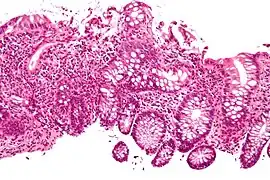

In histology, cryptitis refers to inflammation of an intestinal crypt.

Cryptitis is a non-specific histopathologic finding that is seen in several conditions, e.g. inflammatory bowel disease,[1] diverticular disease,[2] radiation colitis,[3] infectious colitis.